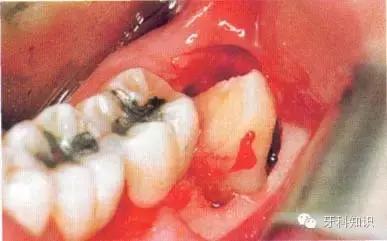

c使用纺锤形的车针( Komet - H162A.314),显露其最大周径至釉牙骨质界。车针末端应进入牙槽窝内壁

d 分牙前应认真确定分牙沟的位置:沿牙体长轴垂直(牙合)面至根分叉。用上述的车针分牙。切割至牙冠舌侧时应格外小心

e分牙已基本完成,远中牙片挺松后即可顺利取出

f 远中牙片取出后即可拔除近中部分。术后应注意牙槽嵴顶的高度。保留颊侧骨板很重要,它有利于牙槽窝和第二磨牙牙槽骨的完全重建